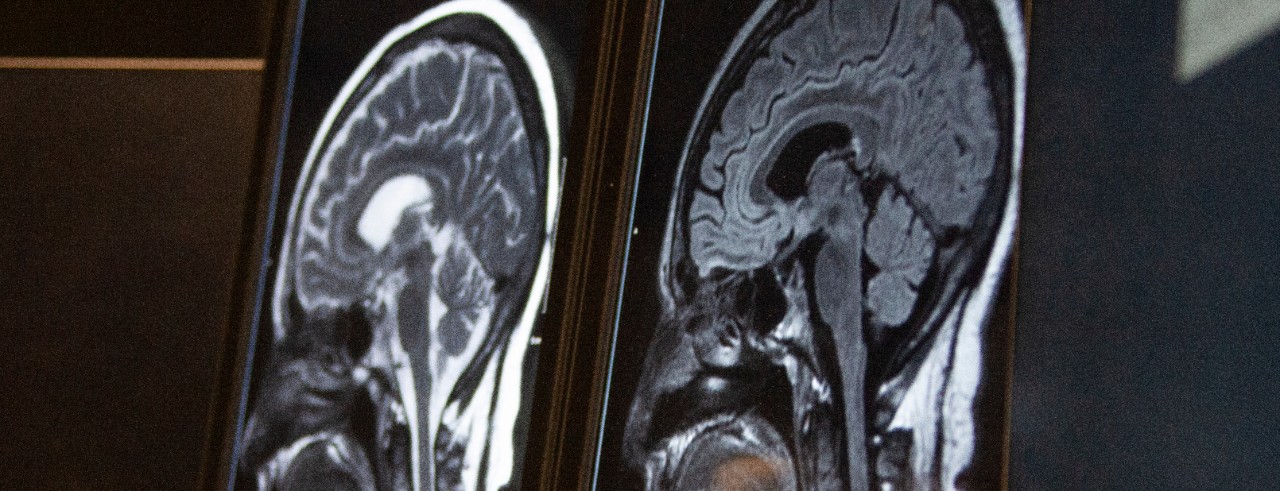

A new study shows that the use of drugs called statins can decrease the risk of stroke caused by intracerebral hemorrhages (ICH), which occur when a blood vessel bursts inside the brain and causes bleeding in the brain. ICH strokes are the most deadly and second most common form of stroke.

Featured photo at top of MRI brain scan. Photo/Ravenna Rutledge/University of Cincinnati.